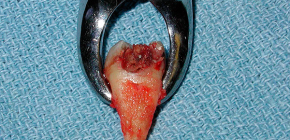

Rimozione delle radici del dente (quando la parte della corona viene distrutta o infiammazione alla radice)

Quando la corona del dente è gravemente danneggiata (ad esempio, dalla carie o a causa di un trauma), spesso sorge la domanda di rimuovere le radici del dente. Può anche accadere che una cisti o un granuloma si formino nella parte superiore della radice del dente a causa del processo infiammatorio - in tali situazioni è talvolta possibile salvare il dente dalla rimozione mediante resezione dell'apice della radice, o anche l'intera radice malata deve essere amputata. Parleremo ulteriormente di ciò che è utile sapere sulla rimozione della radice del dente: vedremo quando, in generale, è richiesta la rimozione della radice, cosa puoi aspettarti nell'ufficio di un dentista-chirurgo e quali problemi a volte sorgono durante la procedura ...